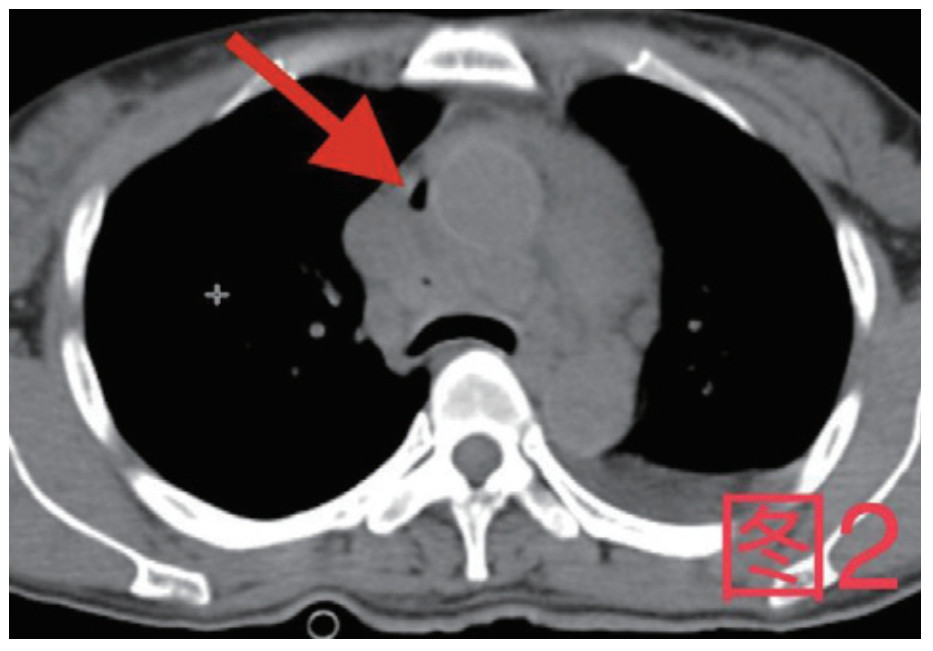

| 图 2 箭头所指为纵隔内积气 |

治疗经过:急诊予美罗培南0.5 g,1次/12 h抗感染,补液支持,心包引流等治疗措施,收住感染科后继续抗感染治疗,期间心包积液培养出白假丝酵母菌,加用氟康唑200 mg,1次/d, 口服,心包积液、左侧胸腔积液引流等措施,治疗10 d后复查胸部CT仍有中大量心包积液伴少许积气,纵隔积气;左侧少量胸腔积液,两肺叶间裂少许积液。对照前片(2020.10.26)心包积气及左侧胸前积液有增多,叶间裂积液新发,心包积液略有减少。右肺下叶感染,左肺下叶膨胀不全,较前右肺下叶感染有吸收,左肺下叶膨胀不全新发。考虑不能排除食管纵隔瘘,予口服碘海醇后胸部CT检查(图 3~6):约胸6椎体水平食管纵隔瘘,瘘口为相应水平食管壁右前方可能;胃镜(图 7):食道距门齿25 cm右后壁见一直径约1.0 cm凹陷,内有一小瘘口。胃镜下予钛夹2枚夹闭瘘口(图 8),同时植入空肠营养管。至此患者病情明确诊断食管心包瘘,患者经以上治疗后心包积液、胸腔积液逐渐减少,于11月13日拔除心包及胸腔引流管,因患者签字回当地就诊,予口服莫西沙星、氟康唑带药出院,出院后随访,患者未回当地医院治疗,仅在家中继续空肠营养管饲喂及口服抗菌药物治疗。

| 图 3 白色箭头所指为气管隆突下方纵隔内积气,红色箭头所指为食管 |